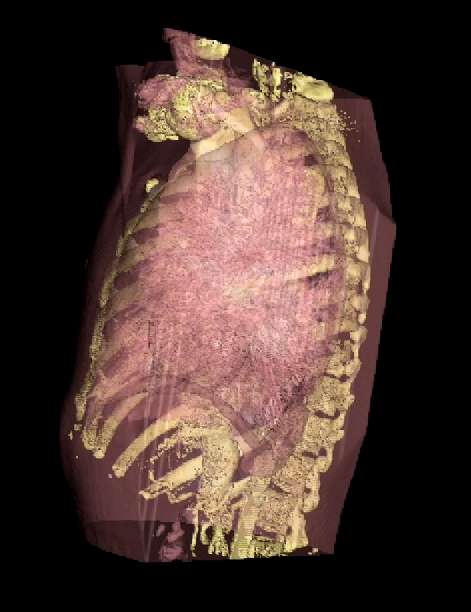

An opacity table can be applied to the results so that surfaces from internal features can also be visualized. As an example, two surfaces have been identified in the following image from the CT scan where voxel values from bone surfaces are coded in an opaque yellow colour and tissue surfaces in a transparent shade of red.